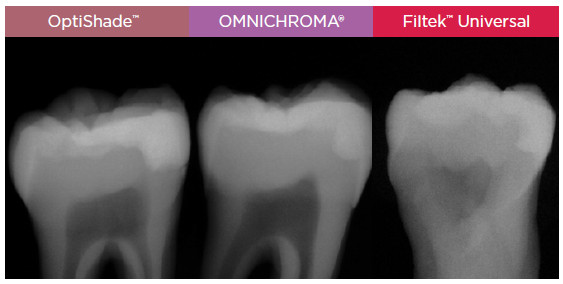

Kiváló röntgenellenállás Minél jobban ellenáll a röntgensugárzásnak, annál könnyebben meg lehet különböztetni a helyreállítást és a fogállományta röntgenképen. Az OptiShade 300% Al röntgenellenállása csaknem kétszer akkora, mint az OMNICHROMA ellenállása.1 |

![]() II. osztályú helyreállításon átesett emberi fog röntgenképe.2 |